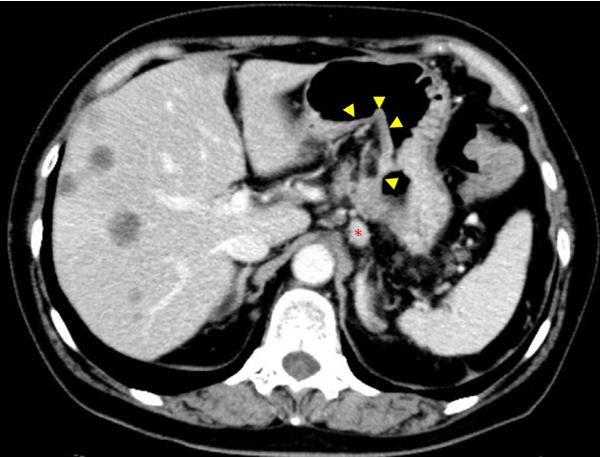

磁共振成像(MRI)显示舌内肌内1.5×2.3×2.0cm的肿瘤。肿瘤在T1加权像上呈低信号,在T2加权像上呈非均匀高信号(图2)。PET/CT发现舌肿瘤;胰腺体肿瘤从脾静脉侵犯到前面肾旁间隙;多发性肝肿瘤;肺肿瘤;盆腔内的腹膜肿块被认为是播散性的(图3A和B)。CT增强扫描显示胰体肿瘤广泛侵犯脾窦静脉至肾旁前间隙。附着在胰腺肿瘤上的胃浆膜层被破坏,肿瘤侵入胃壁(图4)。因为胃的大部分解剖形态保持不变(图4),所以被认为是胰腺癌侵犯胃,而不是胃癌侵犯胰腺。

图4对比增强CT。增强CT显示胰腺体肿瘤。附着在胰腺肿瘤上的胃浆膜层被破坏,肿瘤侵入胃壁(黄色箭头)。胃左动脉淋巴结肿大(红色星号)。然而,胃的浆膜层大部分保持形状。